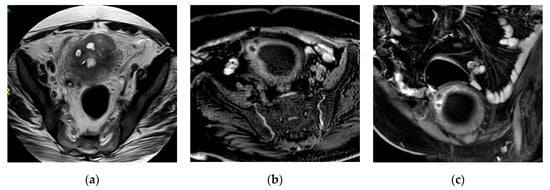

2.13. Eosinophilic Cystitis

| Acute infectious cystitis | Diffuse bladder wall thickening, especially if oedematous at T2 weighted image, urothelial hyperenhancement, perivesical fat stranding. |

| Mural bladder abscess | Intramural/exophytic non-enhancing fluid collection, irregular wall, often thick peripheral enhancement, usually affecting the upper bladder aspect. |